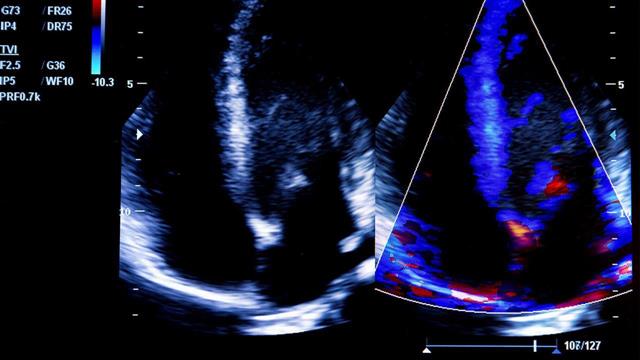

Πρόσφατα δημοσιευμένες μελέτες δίνουν έμφαση στη προστασία των ασθενών με καρδιαγγειακά νοσήματα από τη χορήγηση του εμβολίου της γρίπης.

Σε μία προηγούμενη μετα-ανάλυση δεδομένων από 6700 ασθενείς δημοσιευμένη το περιοδικό Journal of American Medical Association, ο κίνδυνος καρδιαγγειακών συμβαμμάτων ήταν σχεδόν μισός μεταξύ εμβολιασθέντων σε σχέση με όσους δεν εμβολιάστηκαν.

Το όφελος αποδίδεται στην ιδιαίτερη ευπάθεια του ανοσοποιητικού συστήματος που παρουσιάζουν οι ασθενείς με καρδιαγγειακά νοσήματα και τον αυξημένο κίνδυνο επιπλοκών και νοσηλείας με τη γρίπη.